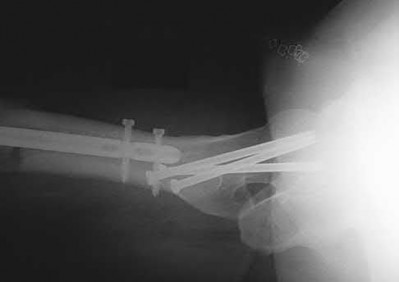

1028) Figures A through C are the radiograph and CT scans of a 42-year-old man who sustained an injury to both of his ankles and underwent surgical repair 2 weeks prior to presentation to your office. One ankle is healing well. On the contralateral side, he reports pain and restricted ankle range of motion. Management should consist of

5. removal of screws, re-reduction of the syndesmosis, and revision fixation.

Corrent answer: 5

This patient has a malreduced syndesmosis. The CT scans clearly show the fibula to be subluxated posteriorly relative to the incisura; therefore, surgical revision is warranted. Revision surgery should include either removal of the current screws with accurate reduction of the syndesmosis and new screw placement or repair of the posterior malleolar fragment, which will in turn reduce the syndesmosis. Addition of an anteriorly directed screw to the current construct will not change the malalignment. Loosening the syndesmotic screws or addition of aggressive physiotherapy will not correct the malrotation of the distal fibula within the incisura which is seen on the CT scan. Outcomes after these injuries are related to the reduction of the ankle mortise.